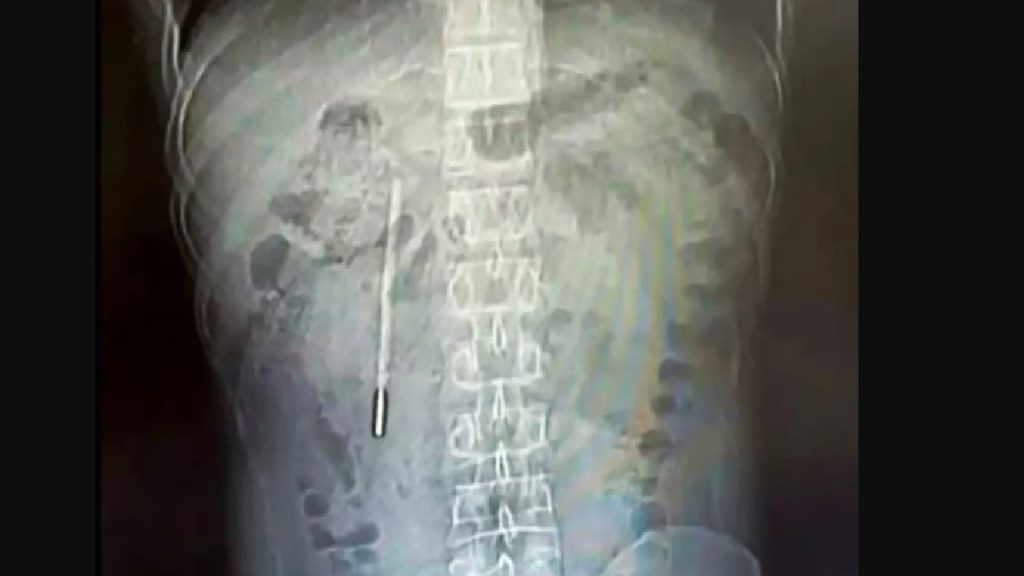

Un bărbat din China și-a descoperit cauza durerilor abdominale persistente: un termometru înghițit în copilărie, acum 20 de ani. Pacientul, identificat drept Wang, a ajuns la spital din cauza unor probleme digestive. Medicii au fost surprinși să găsească un obiect străin în duodenul acestuia: un termometru cu mercur.

Incidentul s-a petrecut în provincia Zhejiang. Wang, în vârstă de 32 de ani, a recunoscut că a înghițit termometrul la vârsta de 12 ani. Nu a spus nimănui despre asta, din teamă. A suferit de atunci dureri abdominale intermitente, pe care inițial le-a ignorat sau le-a atribuit altor cauze.

Intervenția chirurgicală de urgență a fost necesară pentru a extrage termometrul. Acesta era poziționat periculos de aproape de peretele intestinal, crescând riscul unor complicații severe, precum perforații și hemoragii. Din fericire, medicii au reușit să îl îndepărteze fără probleme majore.

Medicii implicați în cazul lui Wang au remarcat norocul acestuia de a nu fi suferit complicații grave în toți acești ani. Extragerea termometrului a fost un succes, iar pacientul se află acum în perioada de recuperare.